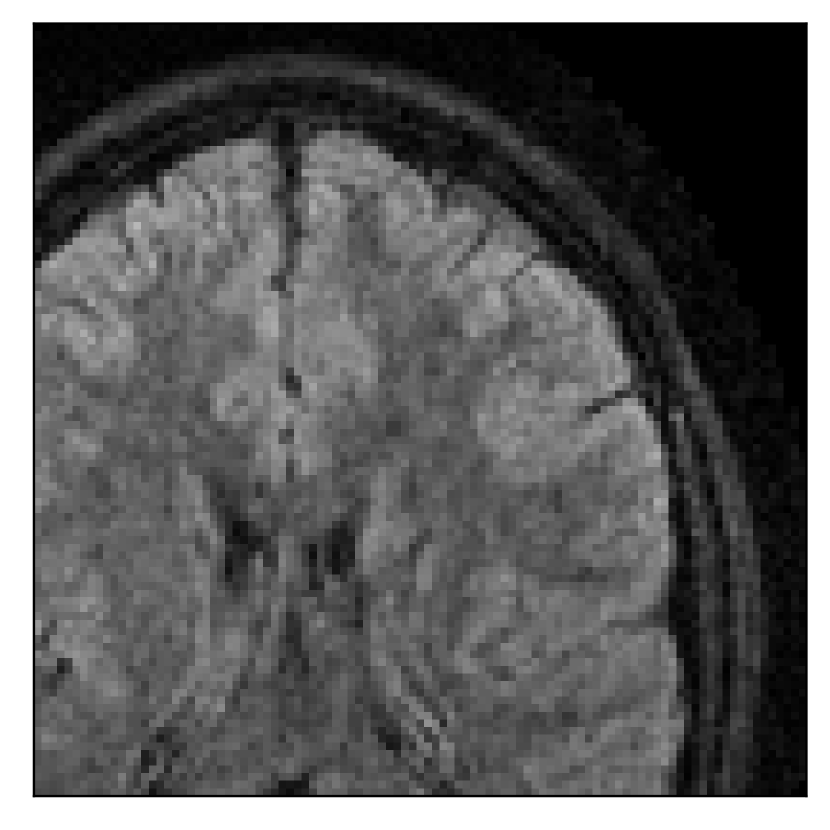

4.1 Experiment 1: robustness test

We gather the results for the robustness test described in Section 3.1 (volunteer 1) in Figures 2, 4, and 6 for motion corruption mechanisms associated to one, two, and five changes of position, respectively. Furthermore, we juxtapose the corrected images with varying degrees of corruption in Figure 8. We observe that the proposed method consistently ameliorates the corrupted scan. The quality indexes based on PSNR and SSIM show only a modest decrease in correction quality as a function of motion complexity (Figure 8).

| Section 3.1, Figure 4 | Sagittal | 25.78 | 27.76 | 0.7263 | 0.7816 |

| Coronal | 28.19 | 29.73 | 0.7847 | 0.8244 | |

| Axial | 27.79 | 29.70 | 0.8104 | 0.8362 | |

| Section 3.1, Figure 4 | T2-FLAIR | Completely corrected | Some blurring | No additional artifacts | Good grey white matter differentiation |